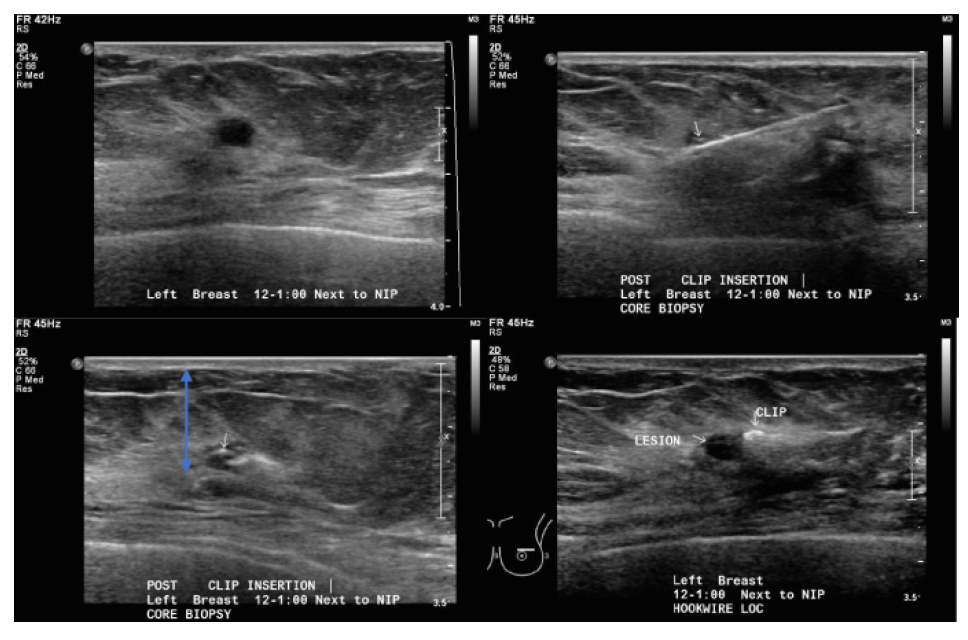

Markers are typically inserted immediately following a core needle biopsy under ultrasound or stereotactic guidance. The marker is deployed through the biopsy needle track into the targeted site.

Post-procedure ultrasound is used to confirm the position of the marker relative to the targeted lesion (if placed under ultrasound guidance). Two-view mammography (craniocaudal and mediolateral oblique) is often performed to document final placement.

On ultrasound, the marker appears as a small echogenic focus with posterior shadowing or reverberation artefacts, depending on the material used. On mammograms, the marker appears as a small, metallic, high-density object on a mammogram, visible as a white or bright spot.

ultrasound-guided core biopsy. Small white arrow: marker.